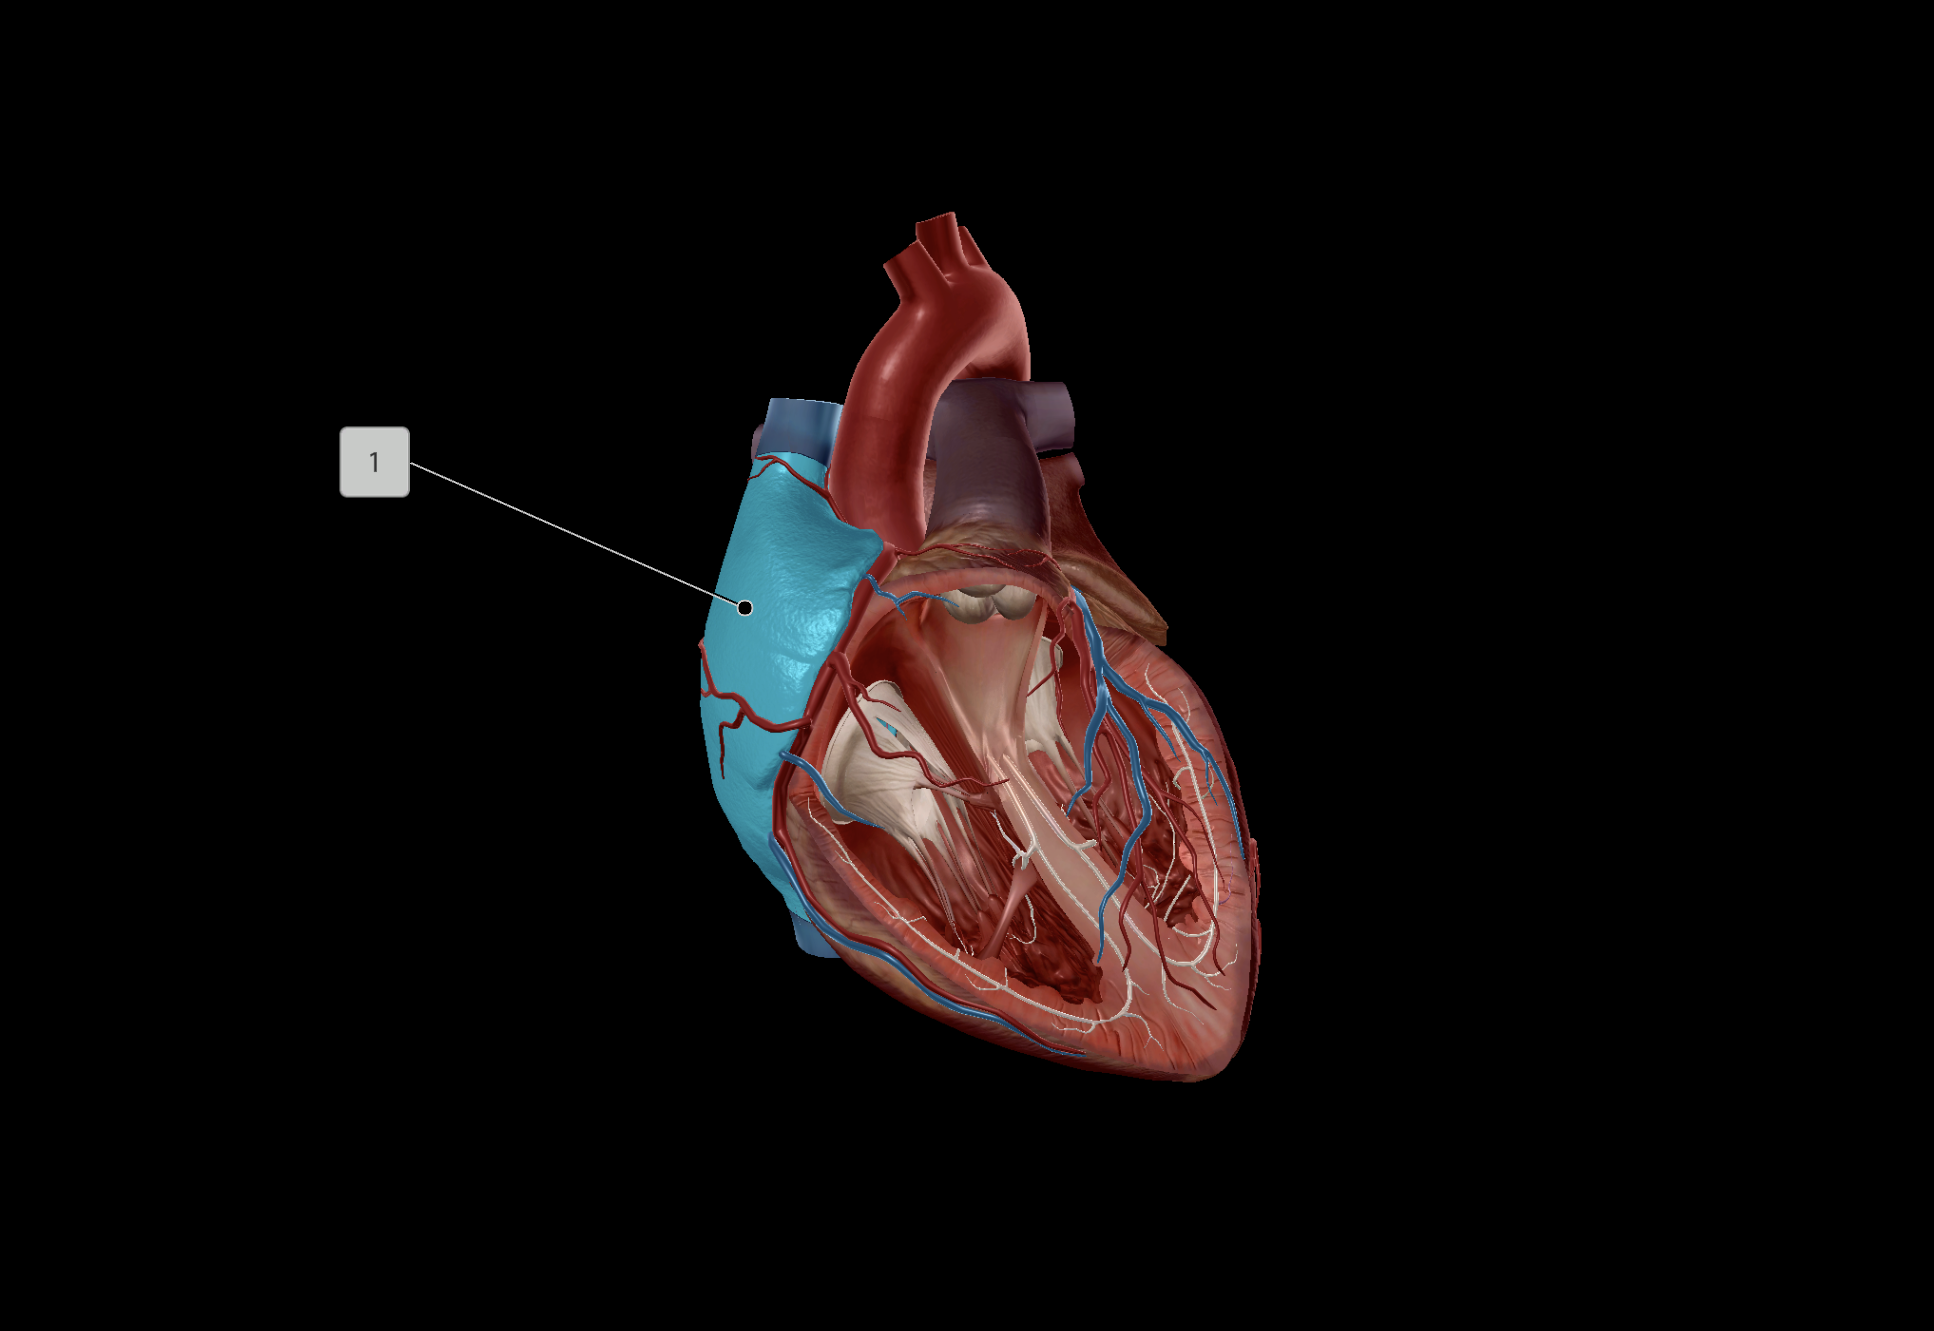

Left Atrium

Right Atrium

Left Ventricle

Right Ventricle

Anterior Interventricular Artery

Circumflex Branch

Coronary Artery

Middle Cardiac Vein

Anterior Interventricular Sulcus

Coronary Sulcus

Great Cardiac Vein

Pulmonary Artery

Pulmonary Vein